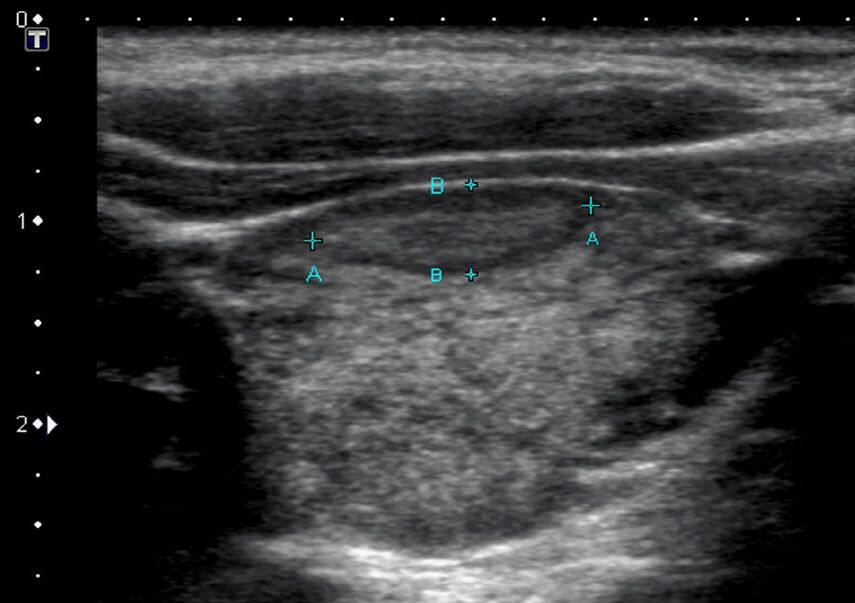

Это способ метод обследования, который позволяет врачу увидеть размеры, форму и структуру щитовидки. На экране ультразвукового аппарата отображаются изображения тканей - это дает возможность выявить отклонения, такие как воспаления, опухоли или узлы.

• Узлы. Это самые частые изменения, которые можно обнаружить с помощью УЗИ. Узлы могут быть как доброкачественными, так и злокачественными. Именно УЗИ помогает определить, насколько узел опасен.